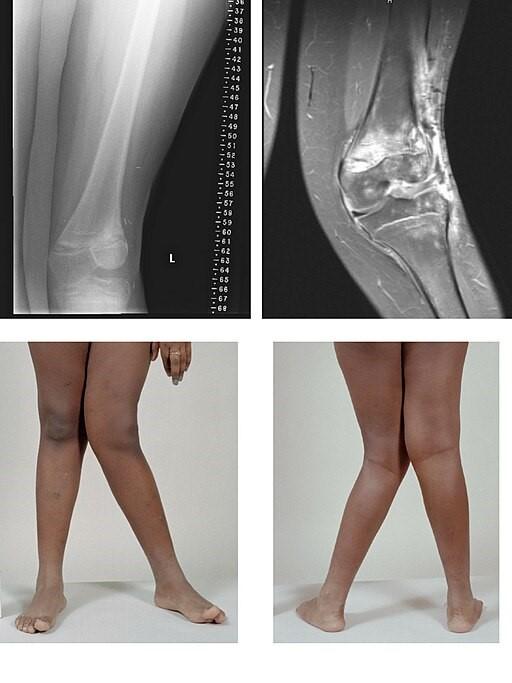

Valgus

By BioMed Central, CC BY 2.0, via Wikimedia Commons